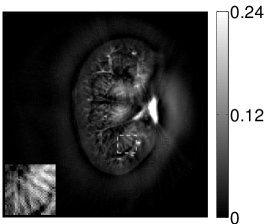

VI-E Results: kidney phantom

The images and EIRs reconstructed by use of the VP algorithm that was based on the 2D imaging model that neglected the SIR are shown in Figures 15 and 16. The latter figure contains results corresponding to different values for the regularization parameter . From Fig. 15, it can be observed that use of the conventional iterative method that utilized the measured EIR resulted in distortions and loss of details in the reconstructed images. Use of the VP algorithm improved the contrast and the details in the reconstructed images (Fig. 15(c) and 16(a)). Furthermore, the images reconstructed by use of the VP algorithm had a more uniform background.

In Figure 17, the results corresponding to use of the 3D imaging model that incorporated SIR effects are shown. The EIR estimated by the VP algorithm is also shown. In Figure 18, images and EIRs reconstructed by use of the VP algorithm with different regularization parameters values are shown.

Similar to the case described above where the transducer SIR was neglected, these results reveal that use of the VP algorithm can produce images with a cleaner background and enhanced spatial resolution than yielded by use of a conventional iterative algorithm that employed the measured EIR. For example, detailed information regarding the vessels near the organ’s periphery was better preserved by the VP algorithm than by the conventional iterative algorithm. These images corroborate our assertion that the VP algorithm can significantly reduce the artifacts and distortions in the reconstructed image. It is also worth pointing out that, unlike the numerical phantom studies, the artifacts and distortions in the images may be caused not only by the inaccurate EIR but also by other factors, such as neglecting acoustic heterogeneities and the variation of the EIRs among the elements of the transducer array. In such cases, the EIR estimated by the VP algorithm represents an effective system impulse response that minimizes the inconsistency between the measured data and the imaging model.